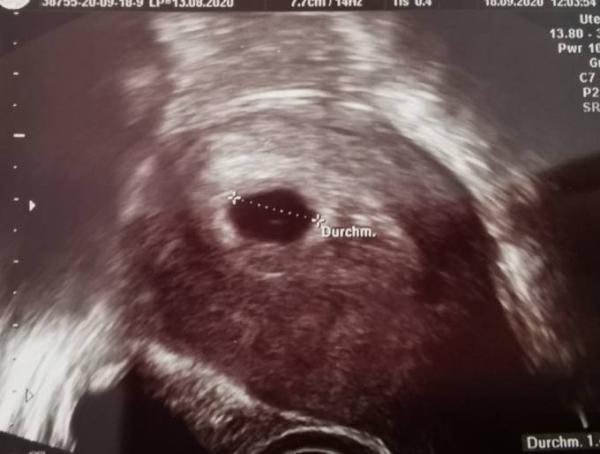

Guten Abend. Hab mich grad mal über die Ramzi Methode informiert und hab jetzt mit lauter Fragezeichen meinen Ultraschall angeschaut. Kann mir jemand sagen, wo meine Plazenta liegt? Hätte Alternativ noch nen Ultraschall aus den ganz frühen Anfängen... Als Baby nur ein Strich war... Bin ich mal gespannt. Liebe Grüße und danke schon Mal

Bild zu Wo liegt die Plazenta? - Forum für Mai - Mamis